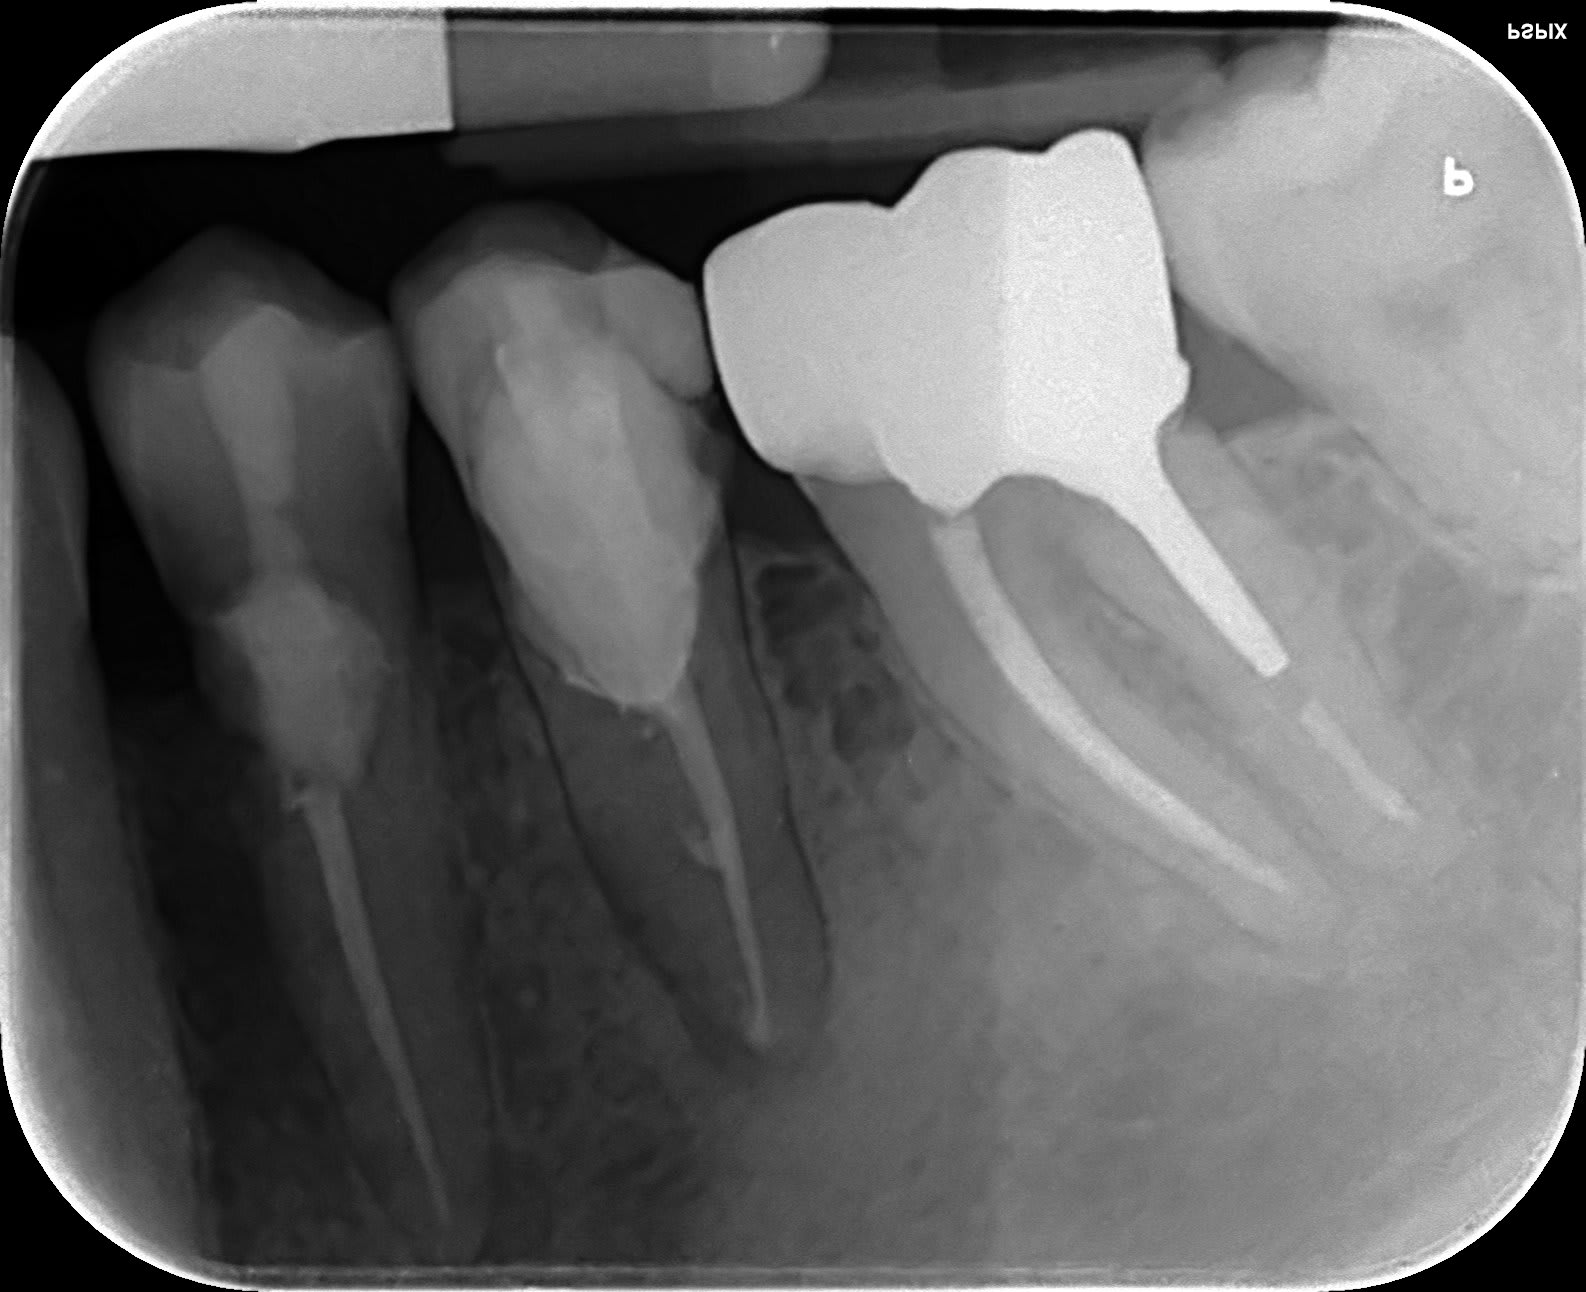

Et j'offre un minitel a celui qui trouve avec quoi je vais sauver cette petite malheureuse 🐁

Sans endo, la 5 c'est un amalgame.

Avant "reconstitutions".

non, pas de vis ni de screw post ni pivot ou autres truc pointu ou pas

voilà c'est fini ... et je vous assure que ça va tenir 10 ans au moins.... enfin si tout se passe normalement et que la patiente ne décède pas avant